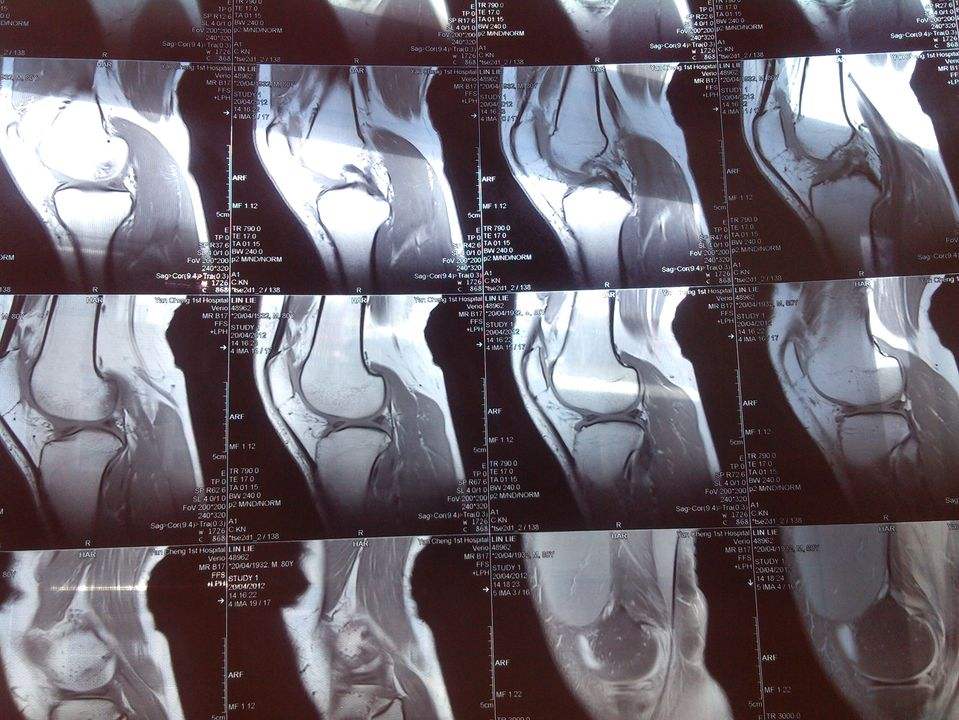

3.核磁共振以及电子显微镜还有原子钟等,都少不了量子力学,否则这些看似距离我们很远,但与我们息息相关,比如核磁共振的造影技术为各位的健康护航,电子显微镜得以让我们窥探到了原子以及原子内部的世界,还有原子钟则是各种通讯的重要保障,当然全球北斗和GPS的核心关键就是原子钟的研制!

膝盖损伤的核磁共振造影,则是X光与CT无法达到的层次!